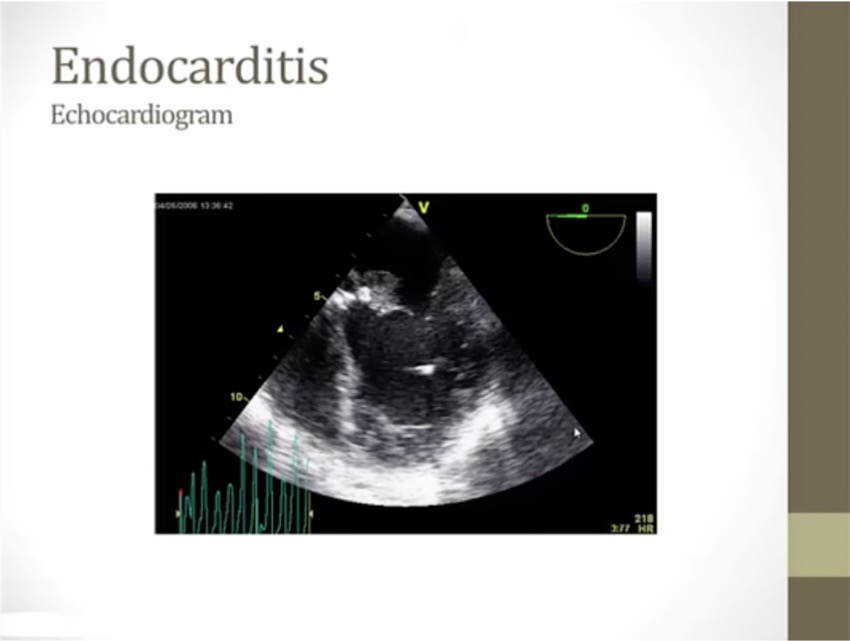

Diagnosis

echodensity

bacterial growth on valve